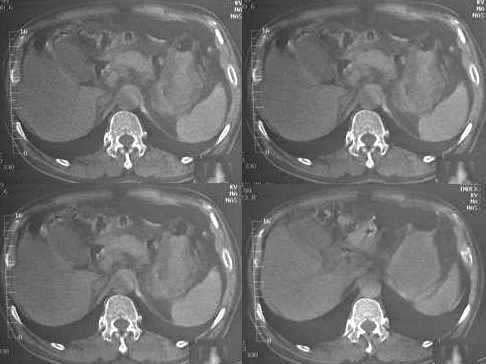

男,60岁,反复头痛,头昏,测血压最高240/120

临床怀疑嗜镉细胞瘤。做ct想了解肾上腺有无肿块。

3.肾上腺没有发现异常?

胆囊旁、肝脏前缘为运动伪影。胃内后方考虑肠管,建议此类检查前喝0.7%泛影葡安800ml后再扫描。

我建议战友让患者检查前晚禁食,于第2天上午空腹{检查前半小时喝清水500-1000毫升,在常规扫描中发现问题后可采用多体位方法,我原来也遇到过内似问题}。